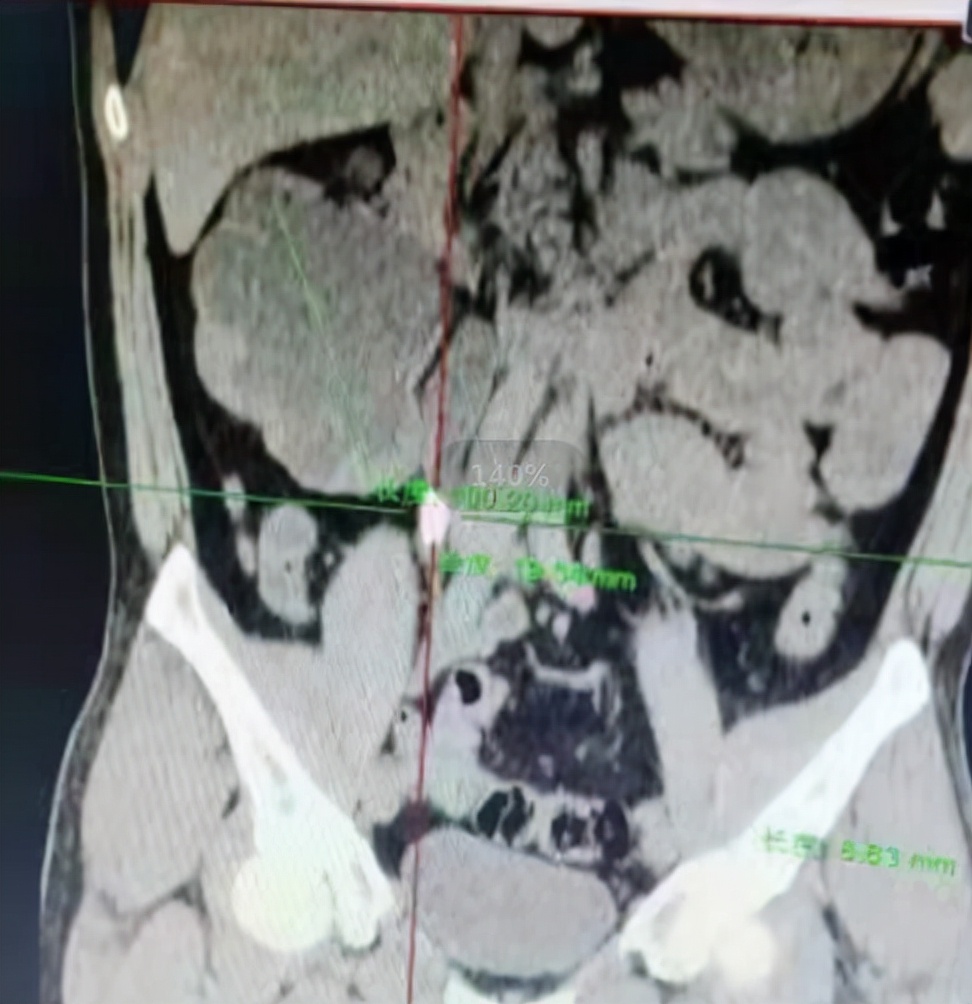

入院后,除了完善血常规、尿常规、凝血、传染病四项等检查外,同时完善了CT、超声检查,其中尿液检查提示肌酐正常,尿酸轻度升高,超声提示左肾形态大小正常,实质回声均匀,右肾体积增大,轮廓尚清晰,实质回声变薄,其内可见大片液性暗区,右侧输尿管上端扩张,于右肾肾盂出口处见一直径约20mm强光团,提示右侧肾脏功能基本已经丧失,右侧输尿管结石。

该患者积水较重,感染情况轻,影像学提示右肾功能基本丧失,但考虑到患者较年轻,因此先予以肾穿刺造瘘,再查双肾ECT,结果提示右肾肾小球滤过率尚可,因此综合考虑后决定给予最大限度碎石取石并保留肾功能。